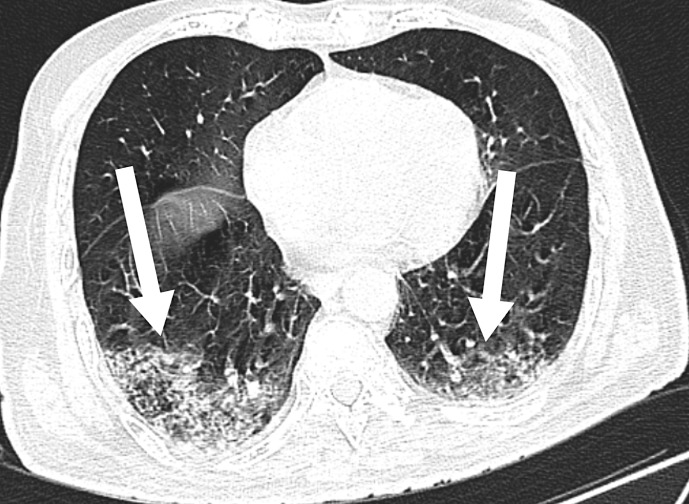

Case presentation: We hereby present the case of a 55-year-old man with a history of diabetes mellitus (potential impact on COVID-19 severity discussed in the supplementary material) presenting with altered sensorium, swelling in the left eye, and involuntary jerky limb movements. Neurological examination revealed neck rigidity, myoclonic jerks, and an extensor plantar response. Brain magnetic resonance imaging (MRI) was performed, which revealed cortical enhancement in the bifrontal, temporal, and occipital lobes. Rapid progression of myoclonus, altered sensorium, and cortical enhancement on MRI suggested Creutzfeldt-Jacob disease. After a thorough workup, the diagnosis was COVID-19 encephalitis with rhino-orbital mucormycosis. The treatment regimen consisted of adequate glycemic control, remdesivir injection, intravenous and retroorbital liposomal amphotericin, and levetiracetam. The patient's condition improved, and he was eventually discharged.